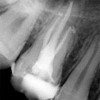

Quando una carie o un trauma colpiscono il nervo, l’endodonzia (comunemente nota come devitalizzazione) è l'unica soluzione per salvare l'elemento dentale ed evitare l'estrazione. Si tratta di una delle branche più delicate dell'odontoiatria: la terapia consiste nel disinfettare, sagomare e sigillare in modo tridimensionale l'intero sistema dei canali radicolari.

Tecnologia di precisione: affrontiamo la complessità anatomica dei canali con protocolli rigorosi per garantire il successo della cura a lungo termine.